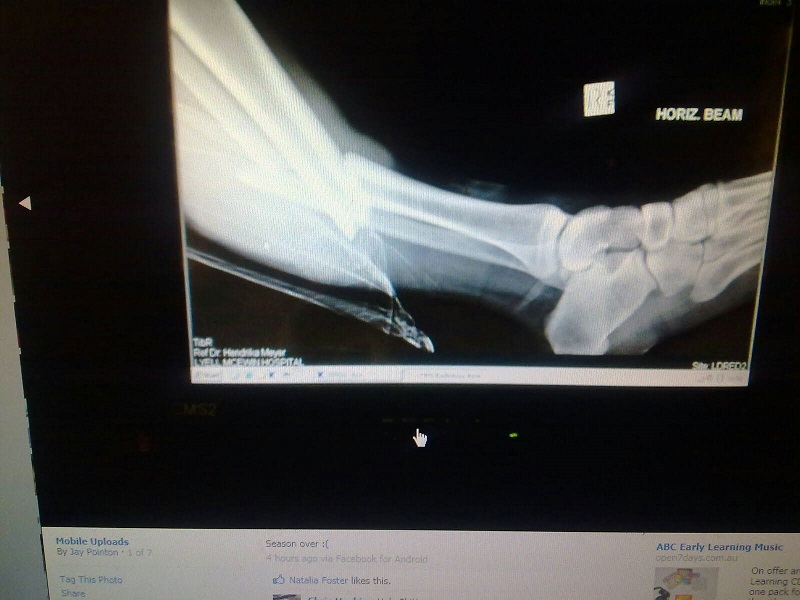

by Johno6 » Fri Mar 28, 2014 4:29 pm

Johno6 wrote:If anyone has a problem with it for whatever reason, he may not want people seeing him without clothes on etc so I apologise to him in advance.

Footy Smart wrote:I think it was Opie from Gaza a few years ago who did ( i think guessing from the photo) ankle and knee dislocations and the tib fib break. BoP might be able to clarify, but the picture was not pretty at all!